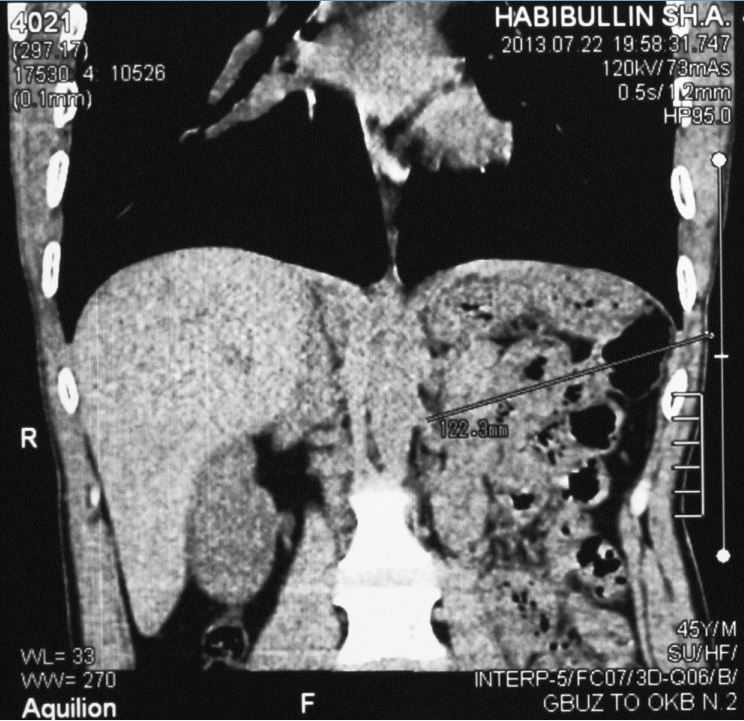

Компьютерная томография потерпевшего

В Тюмени первый компьютерный томограф появился в 2000-е годы. Исследуемое поле современного томографа ограничено какой-либо областью человеческого тела, но для моих целей этого было достаточно. Следователь удовлетворила все мои ходатайства, связанные с исполнением этой хотелки.

Моя задумка заключалась в том, чтобы выполнить компьютерную томографию груди и живота.

Опираясь на сохранившиеся анатомические

ориентиры, измерить длину раневого канала.

За начало раневого канала принят рубец, образовавшийся на коже после заживления колото-резаной раны. На кожный рубец наложена метка, в виде металлической проволоки длиной 1 см.

Раневой канал закончился в левой почке на уровне «сосудистой ножки». Повреждение почечной артерии сопровождалось кровотечением, которое не удалось остановить ушиванием, и поэтому почка была удалена. За дно раневого канала принята оставшаяся после удаления почки культя почечной артерии.

Измерения показали, что расстояние от метки до культи почечной артерии составляет 12,0-12,5 см. Таким образом, клинок ножа длиной 16,5 см погрузился в тело на глубину 12-12,5 см, то есть на 76 %. Сравните это с цифрами, которые заявил защитник: 19,5 см, 6 см, 31 %.